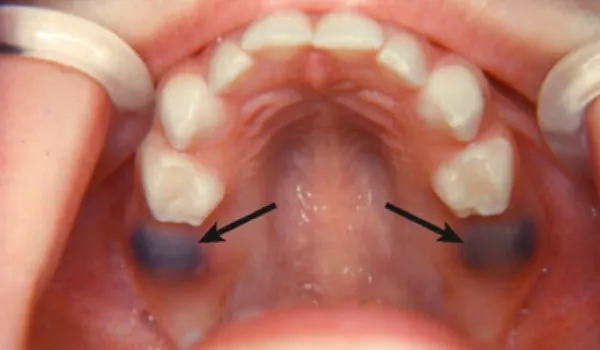

Підшкірна гематома утворюється внаслідок локальних крововиливів у підшкірну клітковину. Інтенсивність відтінку гематоми залежить від глибини локалізації синця і об’єму крові, що вилилася. У міру розсмоктування та руйнування гемоглобіну гематома змінює колір на зеленуватий, жовто-зелений, жовтий. Утворення підшкірної гематоми супроводжується больовими відчуттями, можливе підвищення температури, припухлість тканин.

- Червона гематома-крововиливи в навколишні тканини еритроцитів. Розрив судин, тромбоз.

- Синя гематома (2-3 день)-венозний застій, зміна формених елементів.

- Зелена гематома (4 -5 день)-освіта та виділення гемасидерину.

- Жовта гематома (6 -7 день)-рекомендована терапія, що розсмоктує.